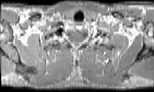

Visible Human male: Sectio transversalis 1300

CT

NMR

Pd T1 T2